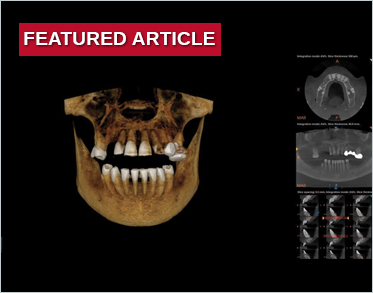

Digital Full-Arch Maxillary Rehabilitation

Isaac Tawil, DDS, MS, Daniel Domingue, DDS, and Scott D. Ganz, DMD